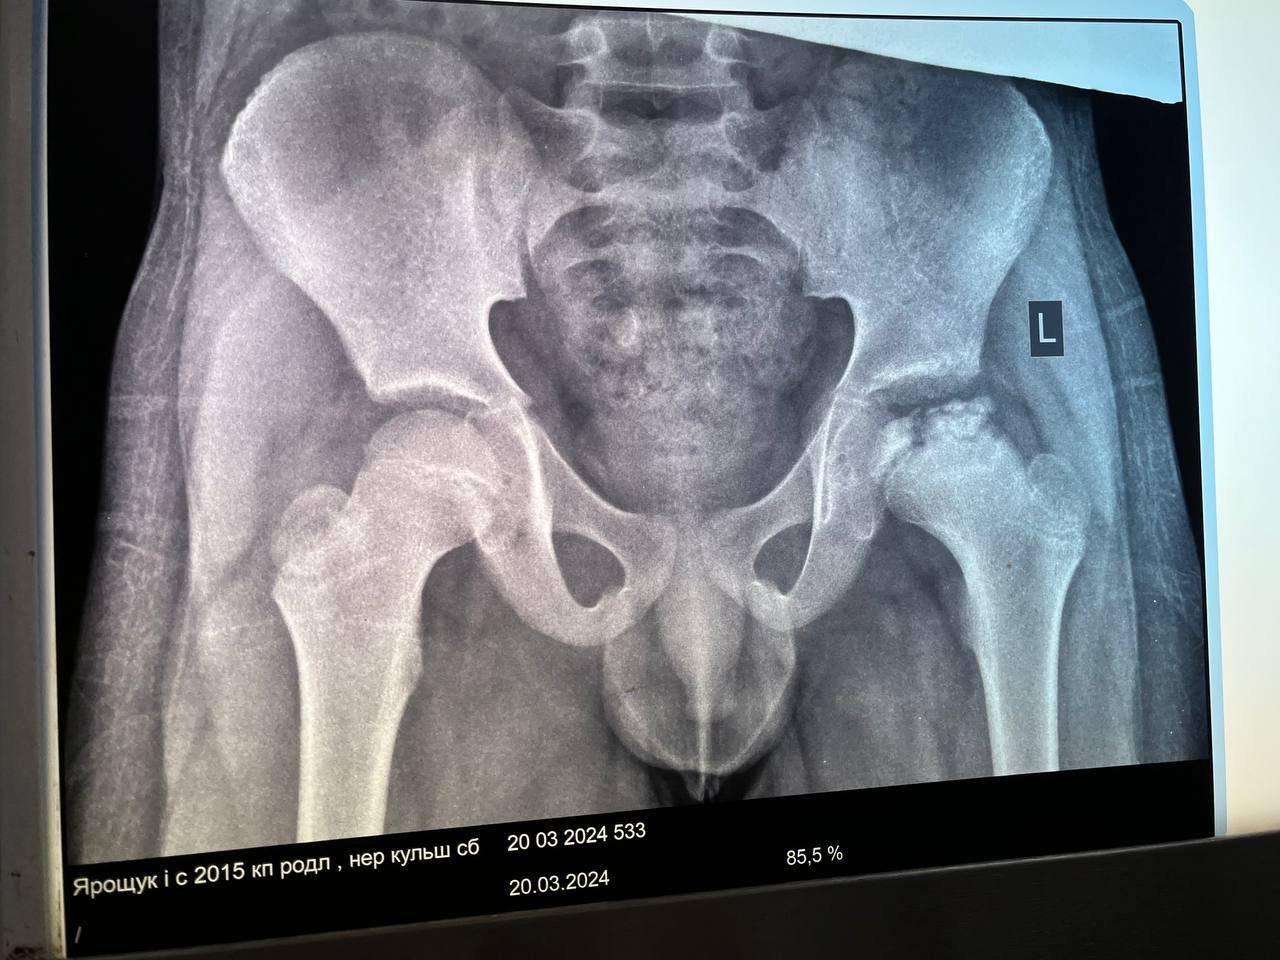

У рівненській лікарні провели унікальну оперцію 9-річному хлопчику з хворобою Пертеса

«У хлопчика був некроз голівки стегнової кістки. У нашій лікарні ми вперше провели таку операцію разом із лікарем з Києва Віктором Філіпчуком, який показав техніку й розповів про переваги малоінвазивного втручання», – розповів ZAXID.NET завідувач ортопедо-травматологічного центру Ігор Яковець.

За словами дитячого травматолога, особливістю малоінвазивного оперативного втручання є тунелізація шийки та голівки ураженої кістки з одночасним введенням пунктату кісткового мозку.

Не пропустіть найважливіше Додайте ZAXID.NET у вибрані в GoogleДодамо, що хвороба Пертеса – це захворювання кульшового суглобу у дітей, викликане порушенням кровопостачання голівки стегнової кістки. Частіше виникає у хлопчиків від 4 до 12 років, рідше – у дівчаток. Переважно пошкоджує один суглоб, однак може бути і двостороннє ураження. Захворювання Пертеса можна повністю вилікувати при ранній діагностиці, а в більш запущених випадках воно може формуватися коксартроз, що призводить до інвалідності.